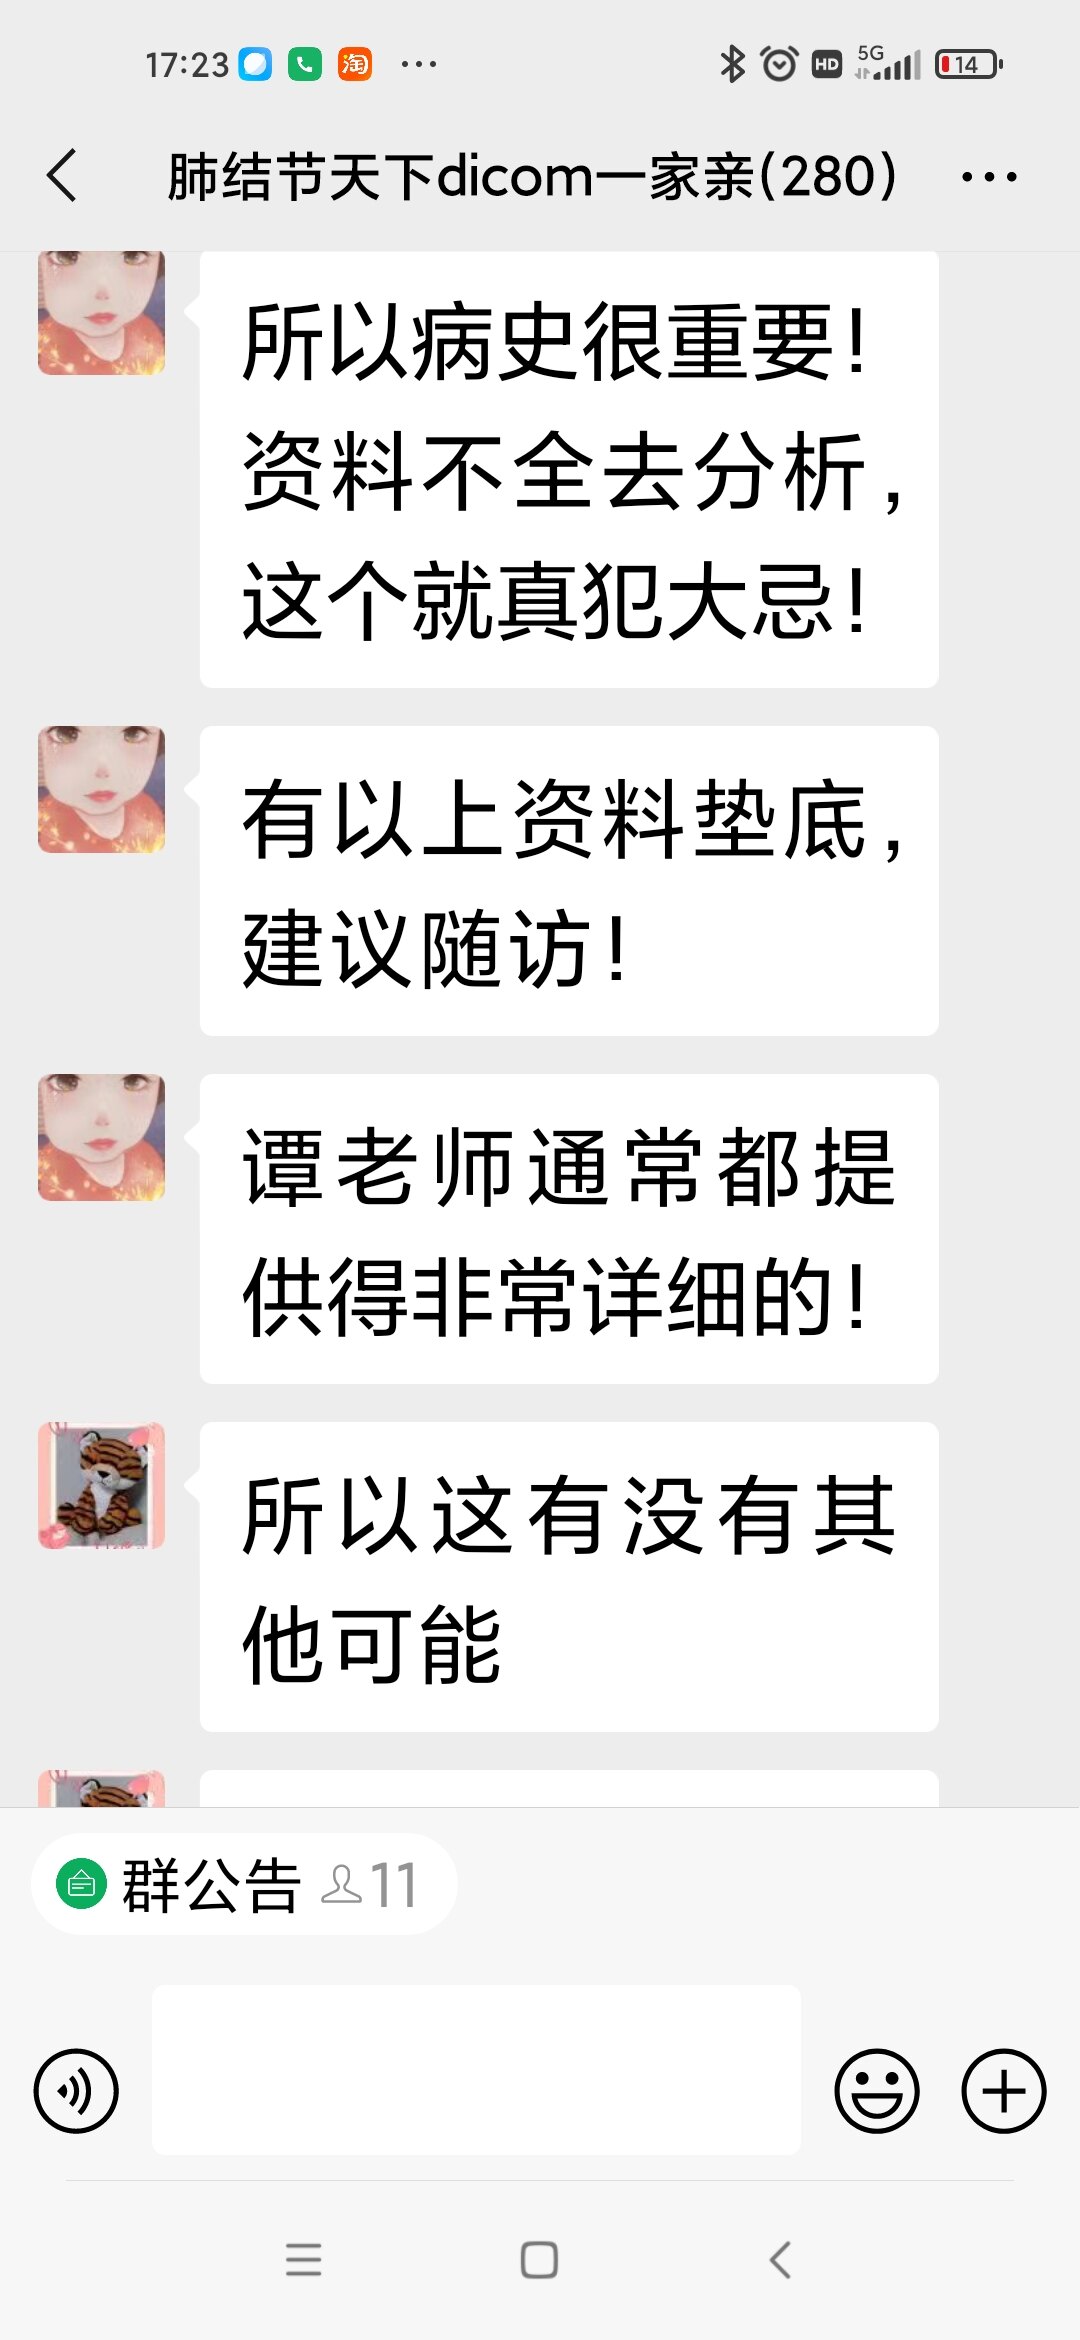

谭先华

副主任医师

武汉市第五医院

放射科

只言片语 之 (7)